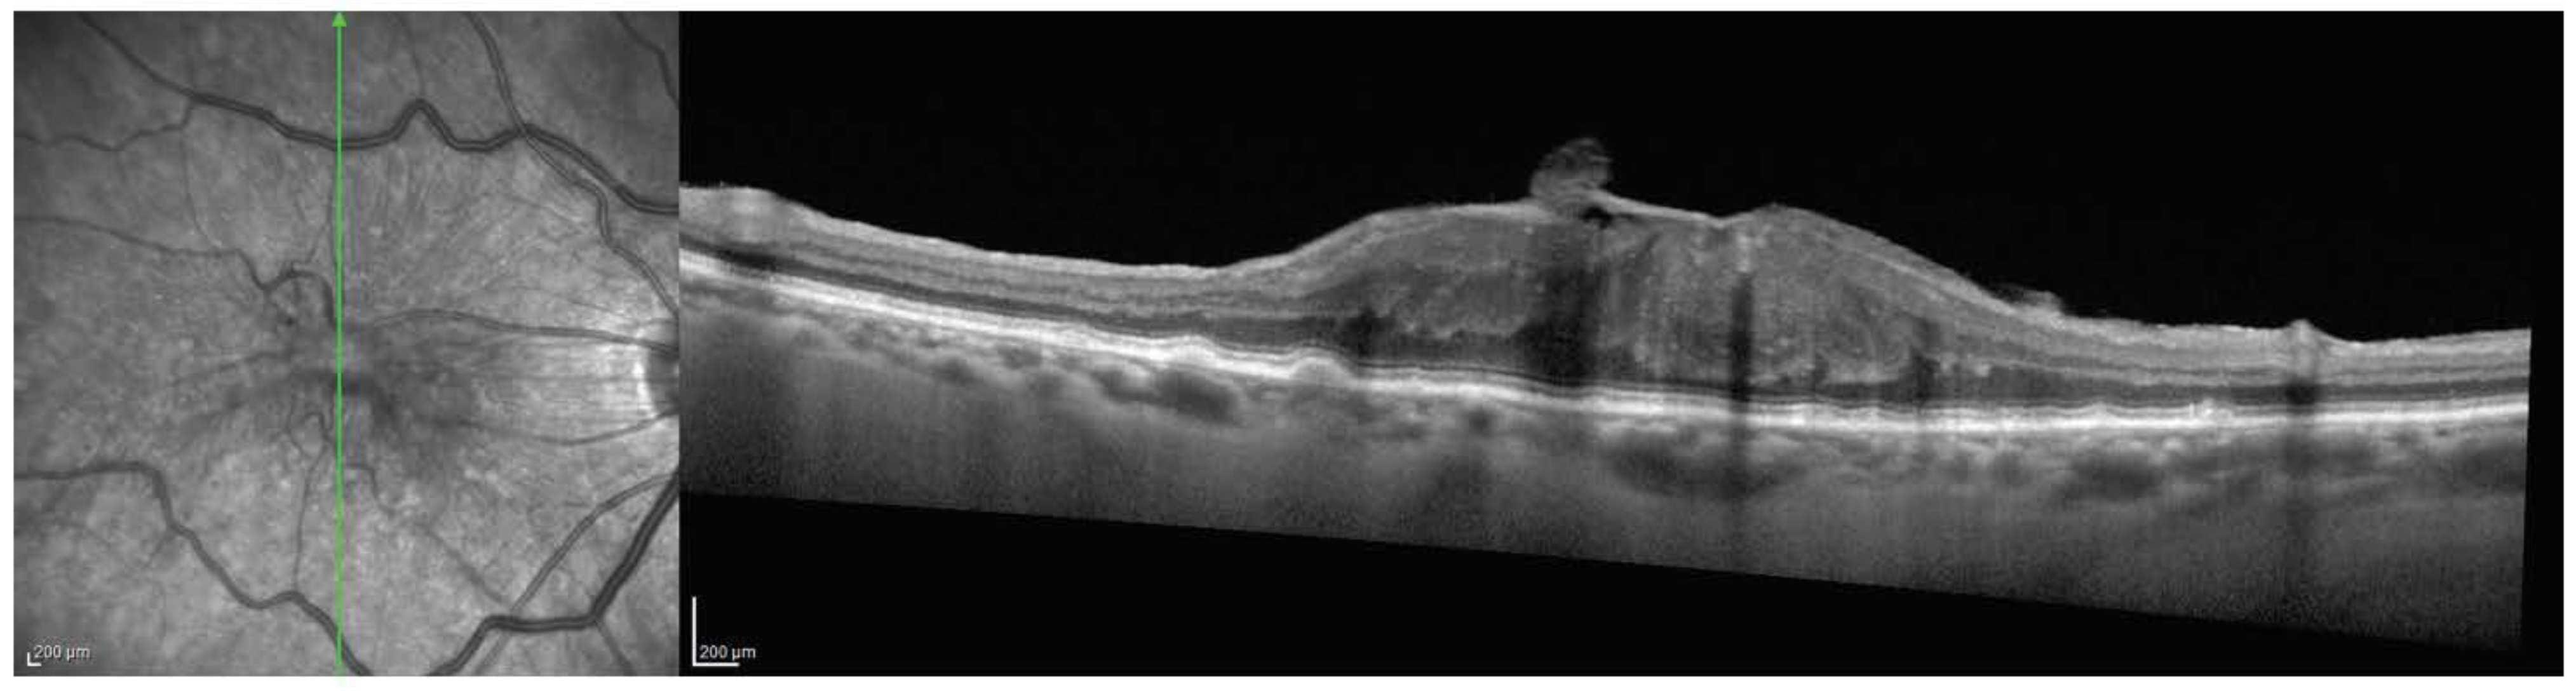

2.2. OCT Grading and Structural Assessment

3.2. Comparison between Structural Parameters in Different Stages of ERM